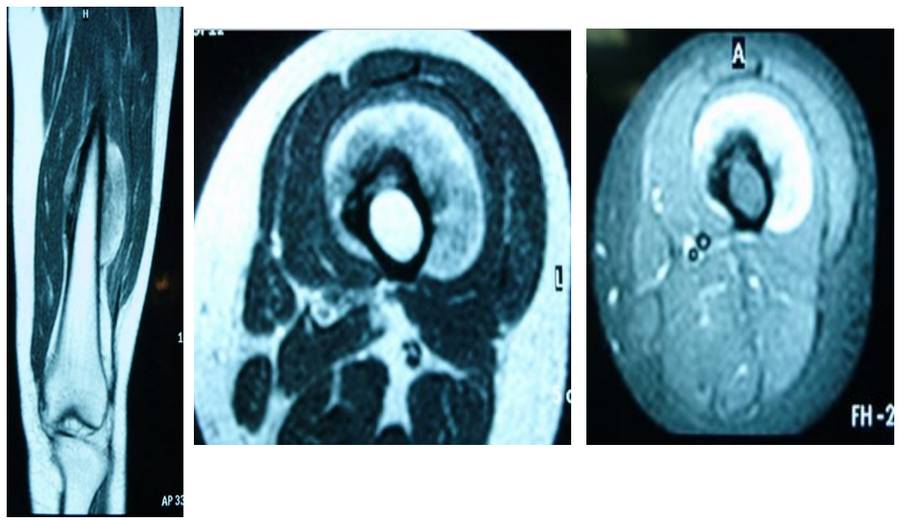

VAKA 13: Uyluk kemiği (Femur) Yerleşimli Osteosarkom

Femur diafiz yerleşimli parosteal osteosarkom nedeniyle geniş rezeksiyon ve vaskülerize fibula ile rekonstrüksiyon yapılan genç kadın hastamız

Ameliyat Öncesi: MR’da femur diafiz anterior yüzeyden kaynaklanan düzenli sınırlı tümör dokusu görülmekte